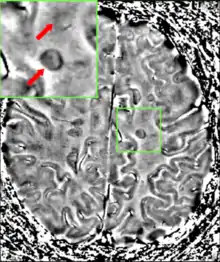

| فرایند از بین رفتن میلین (غلاف چربی روی اعصاب) در بیماری ام اس. حضور گلبولهای سفید و ایجاد پلاک در عکس مشهود است. مقیاس: ۱:۱۰۰ | |

به بیانی روشنتر، اماس به از دست دادن الیگودندروسیتها، سلولهایی که مسئولیت ایجاد و حفظ لایه چربی را بر عهده دارند – موسوم به غلاف میلین – که در انتقال سیگنالهای الکتریکی (پتانسیل عمل) به نورونها کمک میکنند، گفته میشود.[1] این امر به نازک شدن یا از دست دادن کامل میلین، و همزمان با پیشرفت بیماری، تجزیه آکسونهای نورون میانجامد. پس از از بین رفتن میلین، نورون دیگر نمیتواند بهطور مؤثر سیگنالهای الکتریکی را هدایت کند.[3] روند ترمیم، به نام بازسازی میلین، در مراحل اولیه بیماری اتفاق میافتد، اما الیگودندروسیتها نمیتوانند غلاف میلین سلول را بهطور کامل بازسازی کنند.[37] حملات مکرر موجب میشوند تأثیر بازسازی میلین بهطور متوالی کمتر شود و این روند همچنان ادامه دارد تا زمانی که یک پلاک زخم-مانند در اطراف آکسونهای آسیب دیده به وجود آید.[37] این زخمها منشأ علائم هستند و در طول یک حمله تصویربرداری رزونانس مغناطیسی (MRI) اغلب بیش از ده پلاک جدید را نشان میدهد.[1] این امر میتواند بیانگر آن باشد که مغز میتواند تعدادی از زخمهای روی خود را بدون ایجاد عواقب چشمگیر بهطور خودکار بازسازی کند.[1] روند دیگری که در ایجاد ضایعات دخیل است، یک افزایش تعداد استروسیتها غیرعادی ناشی از تخریب نورونهای مجاور است.[1] تعدادی از الگوهای زخم توضیح داده شدهاند.[38]